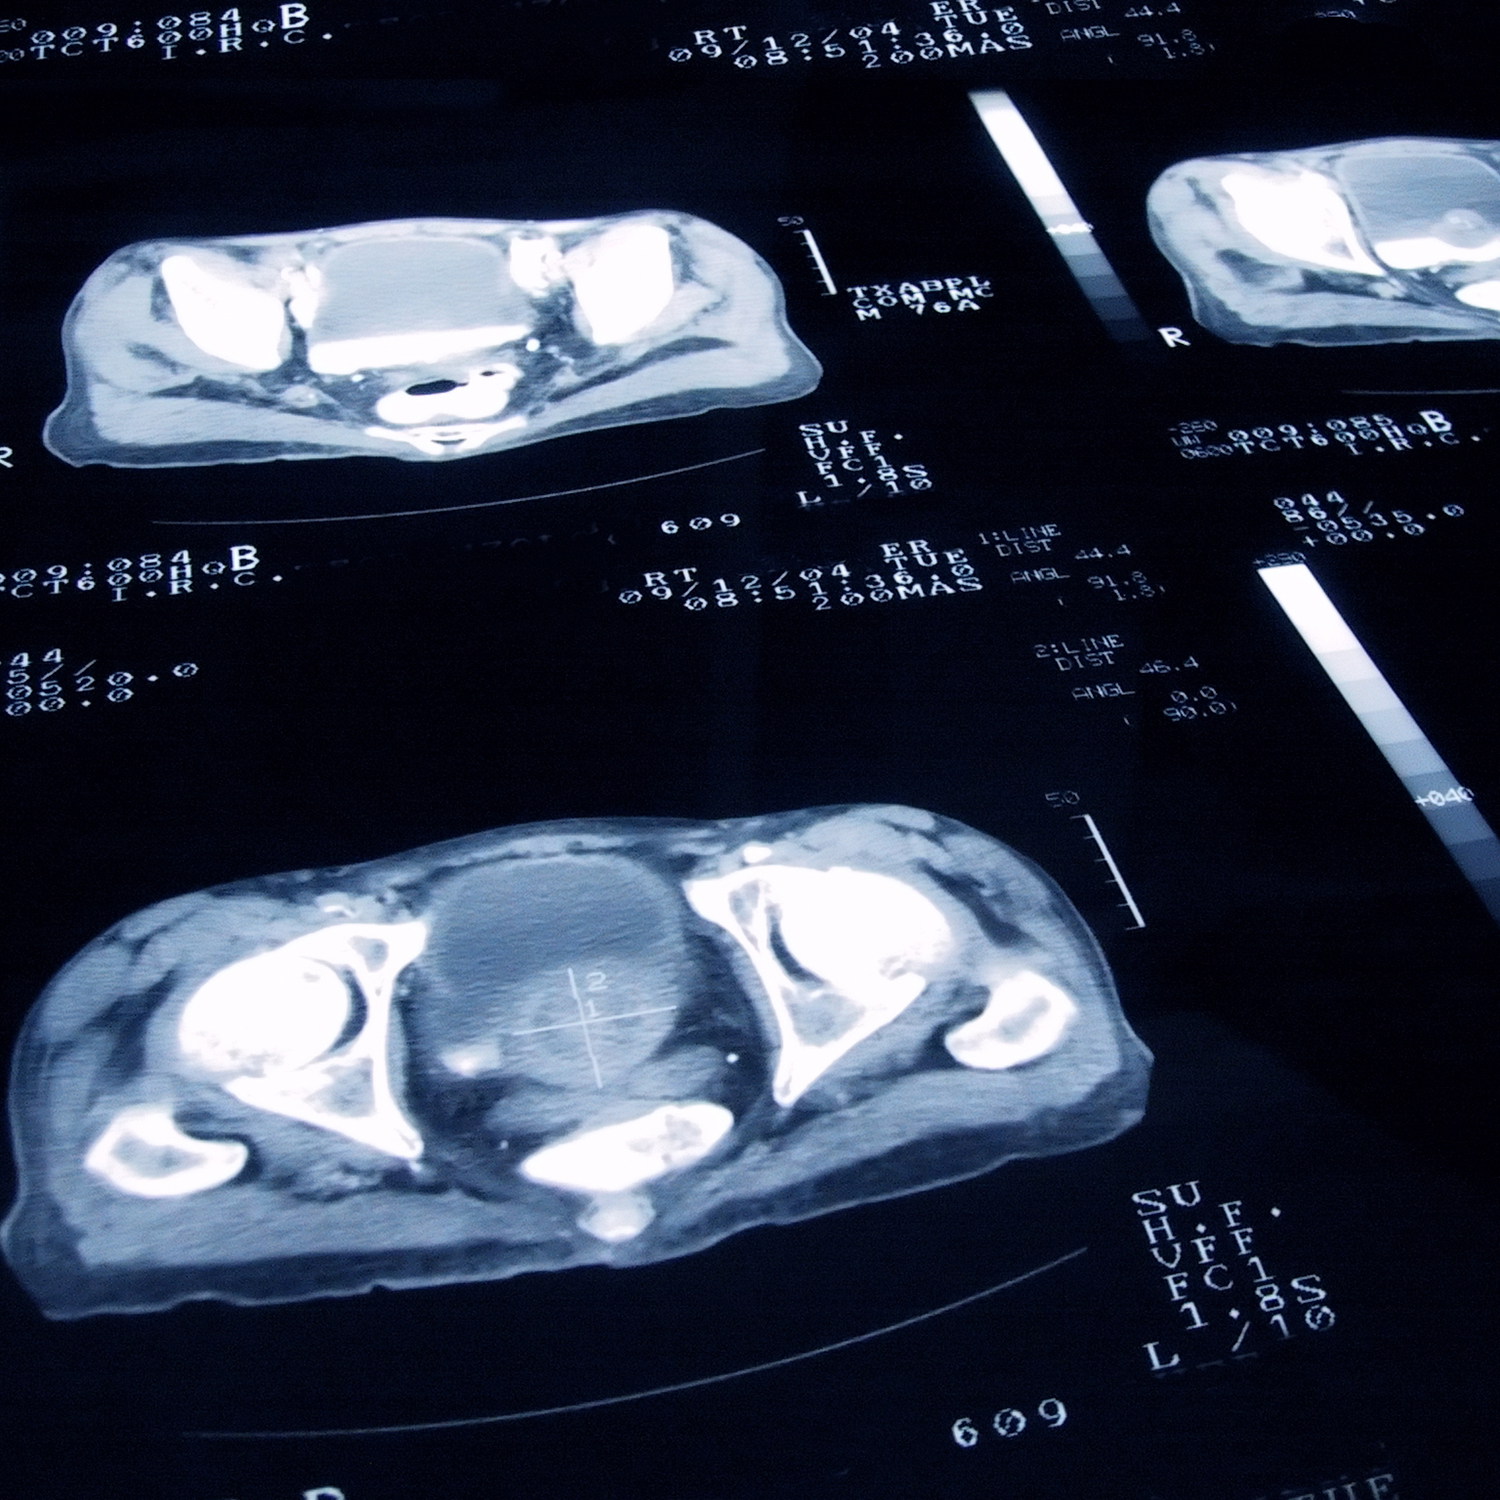

MRI to Diagnose Prostate Cancer – https://debuglies.com

MRI scan of prostate cancer – Santis | Private London prostate cancer …

Prostate cancer, MRI scan – Stock Image – M865/0208 – Science Photo Library

Ct Prostate Cancer Photograph by Medical Body Scans

Ct Prostate Cancer Photograph by Medical Body Scans

Coloured MRI scan showing prostate cancer – Stock Image – M865/0142 …

Prostate cancer: CT findings | Eurorad